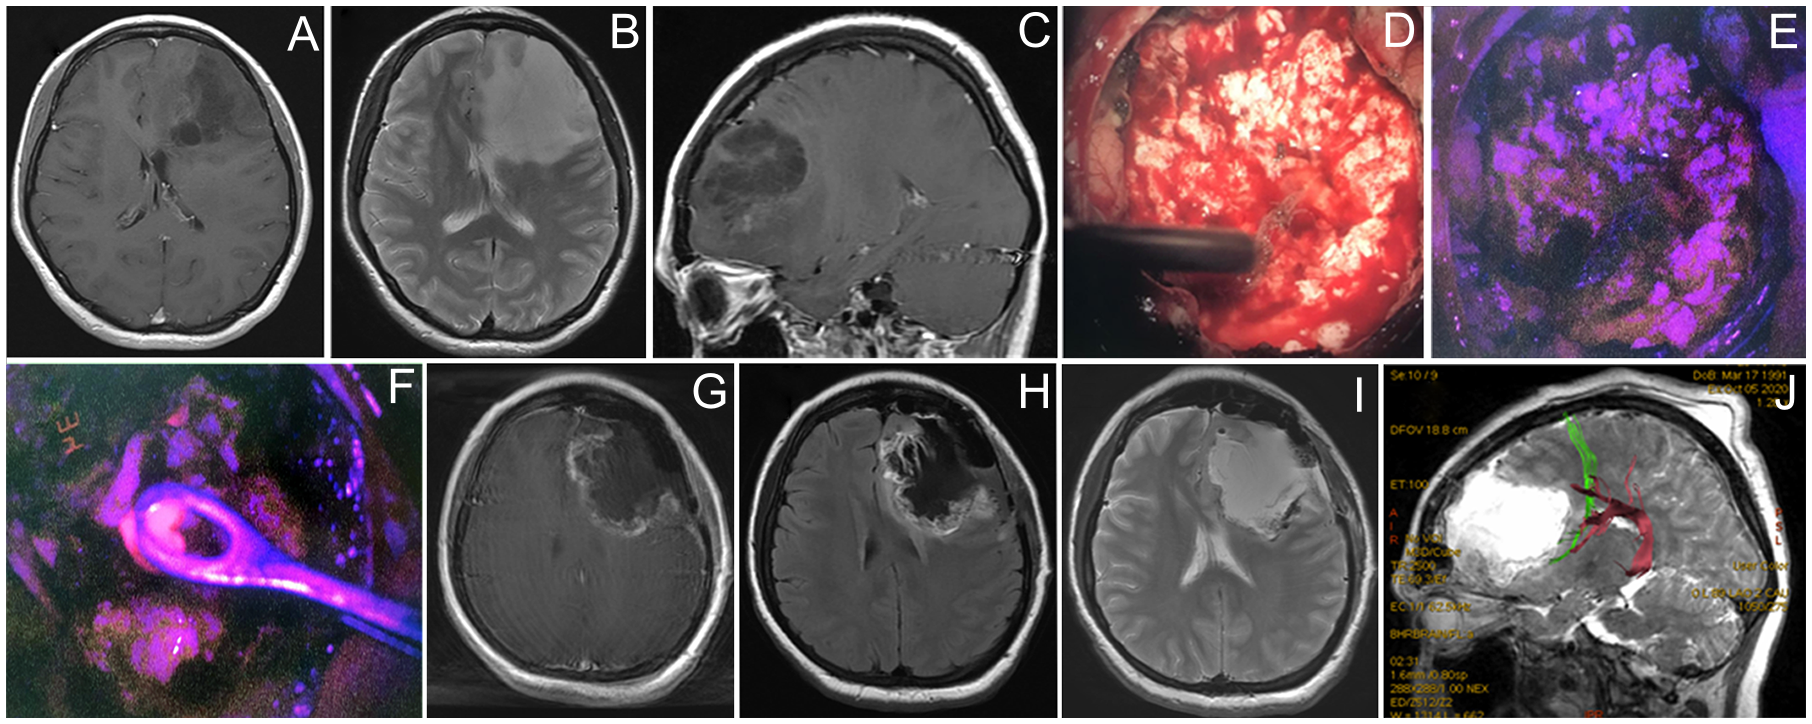

Figure 5

Case 5. A 29-year-old woman with left frontal non-enhancing glioma with a focus of intratumoral fluorescence. Preoperative contrast-enhanced T1 axial (A), T2 axial (B), and contrast-enhanced T1 sagittal MR images showing the tumor (C). Intraoperative photos of the tumor bulk in the white mode (D) and fluorescence mode (E) image demonstrate dim pink fluorescence. A spot of bright fluorescent tissue was identified (F) and taken for biopsy. Postoperative T1 contrast-enhanced (G), T1 (H), and T2 (I) MR images demonstrate partial tumor resection. Postoperative MR tractography overlaid on a sagittal MR T2 image demonstrates frontal аslant tract (green) and arcuate fasciculus (purple) close to the posterior margin of postoperative cavity (J).

A 29-year-old woman Figure 5 presented with a single episode of generalized seizures and was found to have a large non-enhancing left frontal tumor on the MRI. Awake speech mapping was performed in a standard fashion. Cortex and main bulk of the tumor showed no visible fluorescence. However, in the midst of the tumor, a focus of moderate fluorescent positive tissue was found. The remaining tumor showed no visible fluorescence and resection continued with an ultrasound aspirator under continuous dynamic control of subcortical monopolar stimulation. Speech alterations were detected upon subcortical stimulation near the posterior tumor pole in the proximity of AF and FAT; thus, the resection was limited in that direction. Postoperative MRI demonstrated expected residual and overall partial tumor resection (70%). Postoperatively, the patient remained neurologically intact and was discharged home. Histological assessment of the tumor bulk showed diffuse astrocytoma; however, targeted biopsy of the fluorescent area showed IDH 1 mutant anaplastic astrocytoma, which allowed classifying this tumor as Grade 3. The patient received six cycles of temozolomide and 60 Gy radiation therapy. Tumor recurred 30 months after surgery and chemotherapy was resumed. The patient is alive 3 years after the surgery.